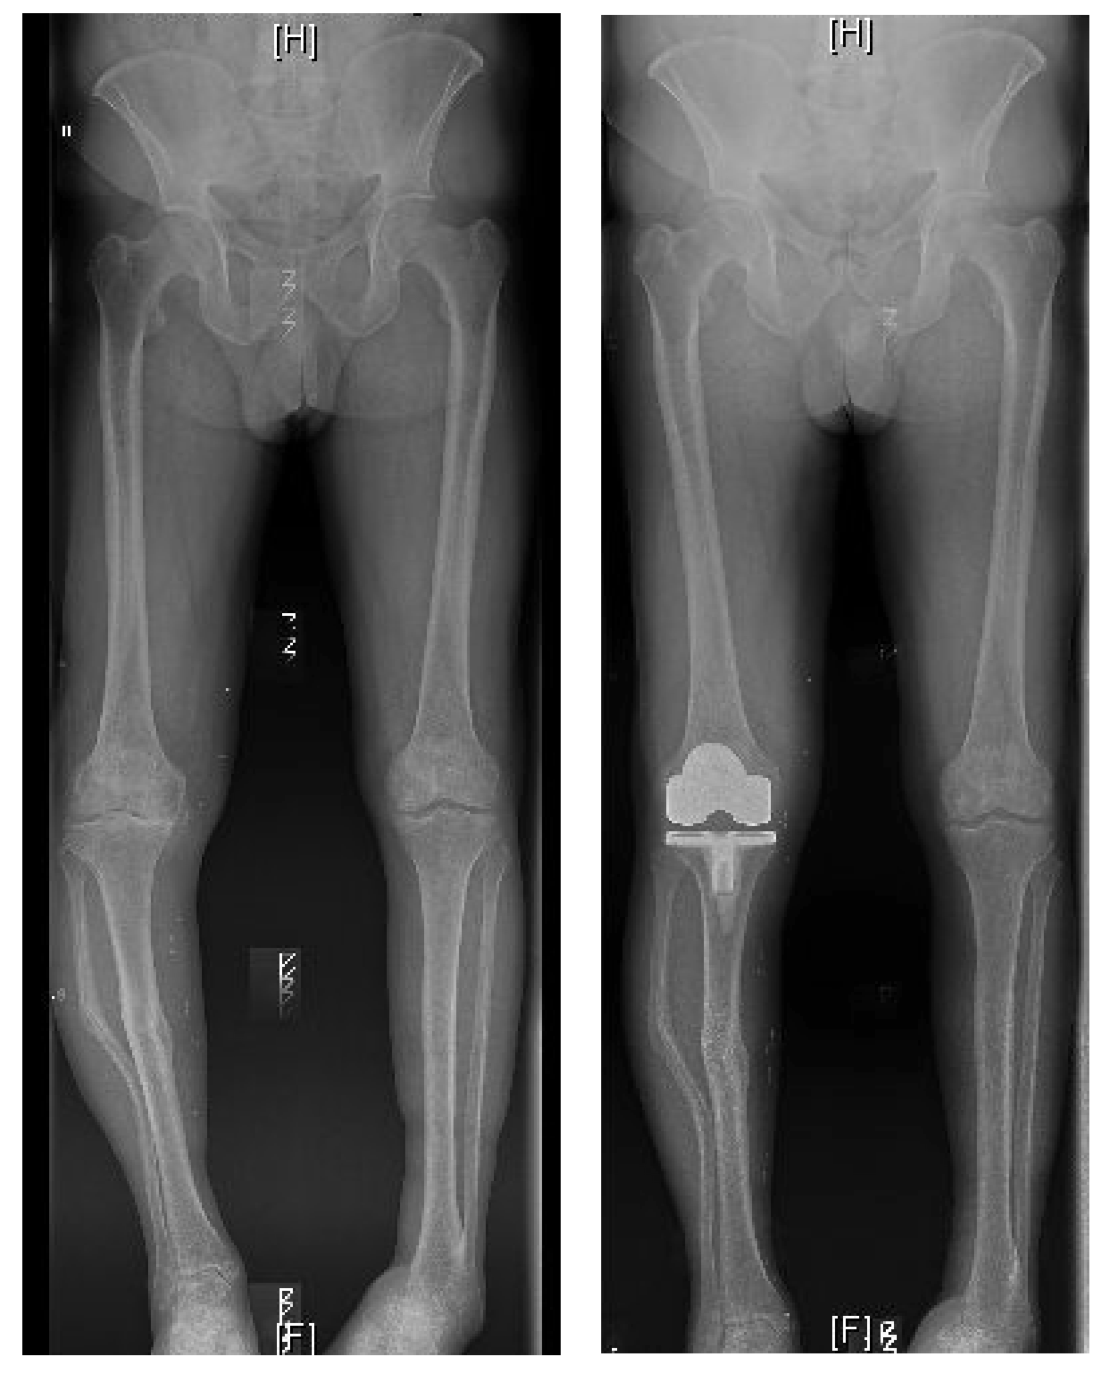

HIGH TIBIAL OSTEOTOMY

I am now more active than I have been in many years

I had High Tibial Osteotomy surgery with Mr Mihai Vioreanu in November 2016. Having osteoarthritis in my left knee left me unable to enjoy a normal active life without pain if I spent long periods walking or standing.

"Enjoying an active life"

I had High Tibial Osteotomy surgery with Mr Mihai Vioreanu in February 2015. I had been in terrible pain with my knee in 2014 following arthroscopic 'clean-out' performed in a different hospital. Mr Vioreanu was excellent during all my consultations with him. He spoke openly and plainly about the surgical procedure in layman's terms. He thoroughly discussed all the pros and cons involved. Mihai was always ready and available to assist me after surgery. I am now back to a normal lifestyle and en

"Best decision I made"

I decided to go for it and can honestly say it was one of the best decisions I made. 6 months later and I'm walking and hiking pain free, performing all manner of exercise and am working towards running/jogging.

BILATERAL HIGH TIBIAL OSTEOTOMY

"Mihai professionalism and experience is top class"

Mihai put a plan in place over three years to carry out surgery on both legs. The surgeries were a great success.